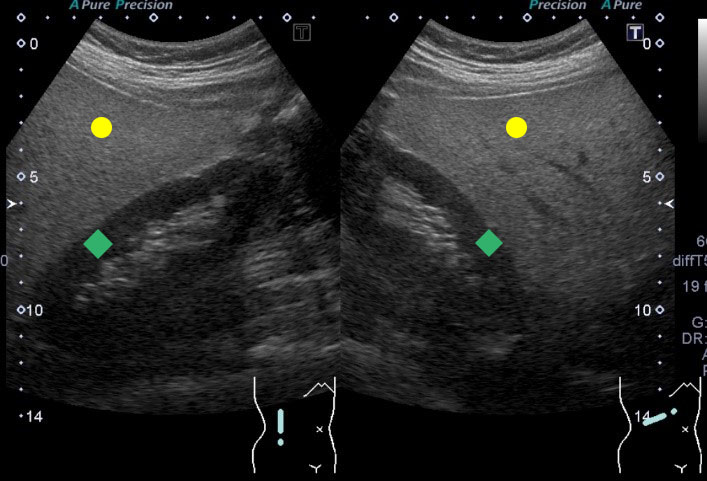

脂肪肝の腹部超音波画像

この症例では肝が白っぽくなっており、肝への脂肪沈着を表します。